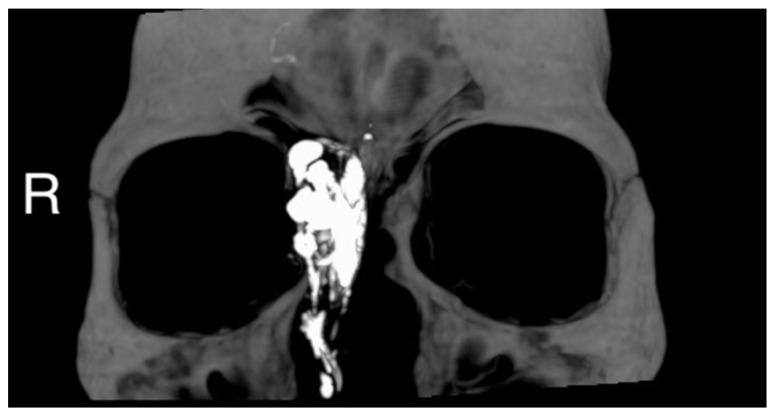

Glomangiopericytomas are a rare type of sinonasal tumors with high relapse rates. Endoscopic sinus surgery is the classical technique to remove such tumors. Here we report a case of sinonasal glomangiopericytoma with orbital extension, infrequently described in the literature. A 50 year-old woman was referred to our hospital because of a right paranasal painless swelling, which appeared 9 months ago and was slowly increasing in size since her first visit. A Magnetic Resonance Imaging (MRI) revealed a tumor (18 × 25 × 37 mm) centered on the right ethmoidal cells, with adjacent nasal bone erosion and a right orbital invasion. The tumor was removed with a combined surgical approach (endoscopic and trans-sinusal frontal approach) after pre-surgical embolization. Based on the results of the histopathological examination, the diagnosis of a glomangiopericytoma was confirmed. The patient was discharged after one week, and an uneventful long-term follow-up.

摘要

血管外皮细胞瘤是一种罕见的鼻窦肿瘤,复发率高。鼻内镜鼻窦手术是切除此类肿瘤的经典技术。在此,我们报告一例鼻窦血管外皮细胞瘤侵犯眼眶的病例,该病例在文献中鲜有描述。一名50岁女性因右侧鼻旁无痛性肿胀前来我院就诊,该肿胀于9个月前出现,自首次就诊以来大小逐渐增大。磁共振成像(MRI)显示一个肿瘤(18×25×37mm),以右侧筛窦为中心,伴有相邻鼻骨侵蚀和右侧眼眶侵犯。术前栓塞后,采用联合手术方法(鼻内镜和经鼻窦额部入路)切除肿瘤。根据组织病理学检查结果,确诊为血管外皮细胞瘤。患者术后一周出院,长期随访情况良好。